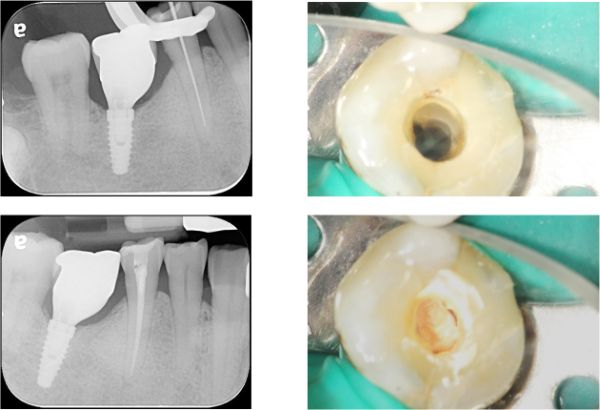

顯微根管治療

製作玻璃纖維釘柱

治療後根尖照,透過牙冠修復受損結構,患者逐漸適應